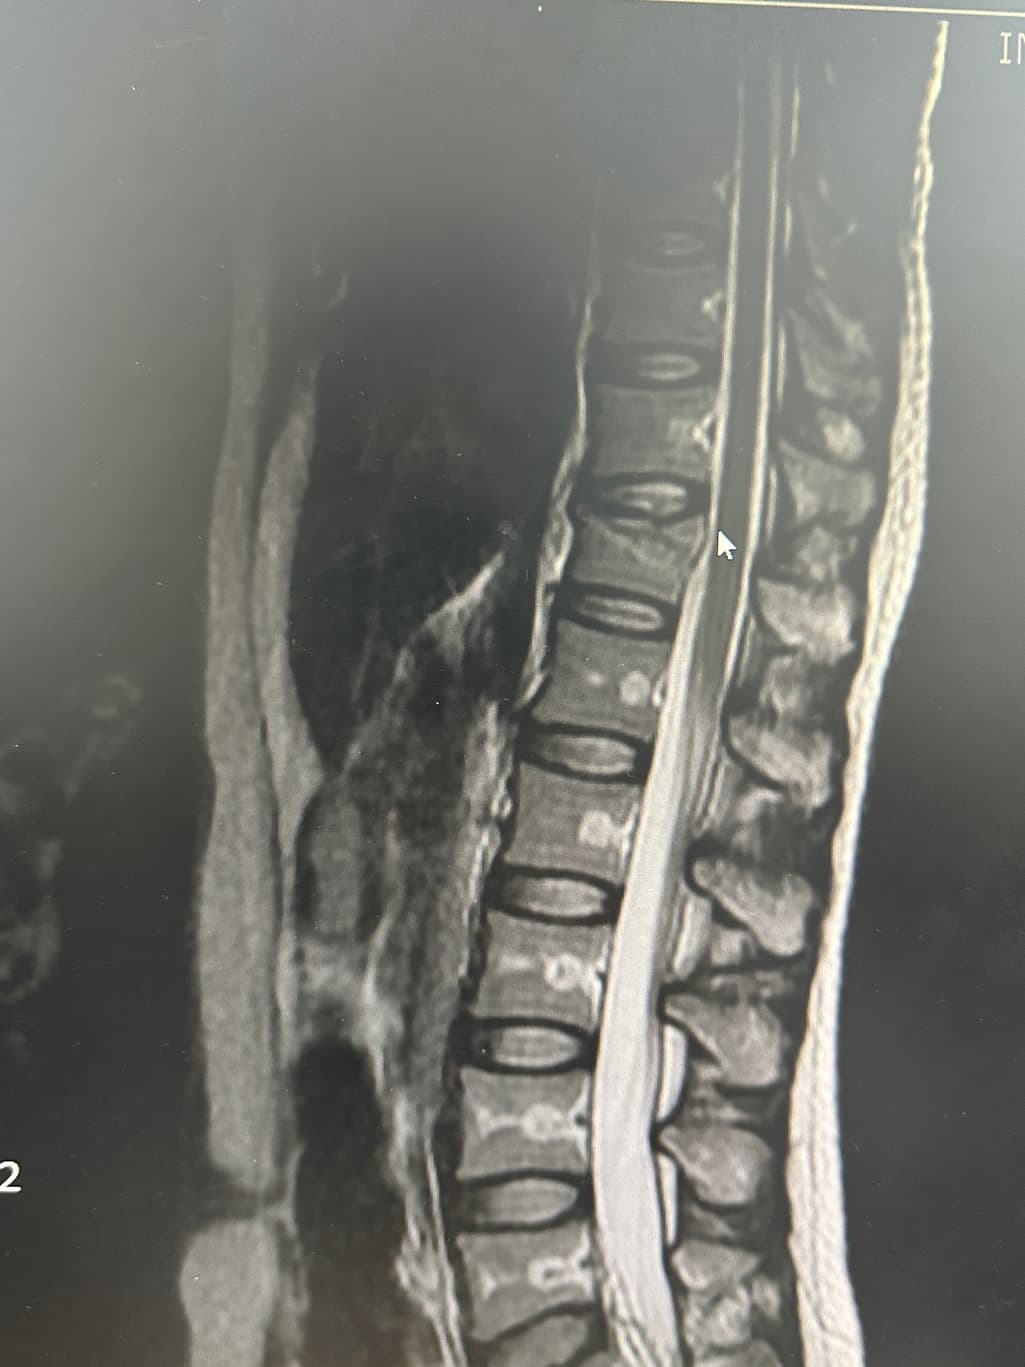

아랫부분들 직사각형 안에 가운데에 하얗게 심지처럼 보이는건 뭘까요?? 뼈가 약해진건가요?? 다른 사람들 척추 mri 보면 안저렇던데 불안해요 의사쌤에게 여쭤보는걸 까먹었네요

MRI 영상 왼쪽아래에 보면 이게 어떤 setting으로 촬영한건지가 나와있습니다.

T1, T2, T2 fat supression 이런식입니다.

이걸 알아야 하얗게 보이는게 뭔지 예상해볼 수 있습니다.

아마 다른 사람들에서 안보인 이유는 다른 세팅의 영상을 보셨기 때문일겁니다.

뼈가 약해져서 이렇게 보이는건 아니니 걱정 안하셔도 되겠습니다.

mri에서 뼈 속에 보이는 하얀 줄기 같은 모습은 보통 골수의 신호 변화로 정상적인 변이일 수도 있고 혈관, 지방 변성, 경미한 골수 부종처럼 특별히 병적이지 않은 경우가 많습니다.척추체가 약해져서 골다공증처럼 무너진 경우는 대개 모양이 찌그러지거나 골절 흔적이 같이 보입니다. 사진만으로는 정확히 단정할 수 없지만 담당 선생님이 따로 설명하지 않았다면 심각한 소견은 아닐 가능성이 큽니다!